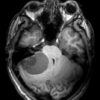

U nguyên bào mạch máu

» Thông tin: Nam giới – 25 tuổi.

» Lâm sàng: Đau đầu + Nôn + Rối loạn thăng bằng.